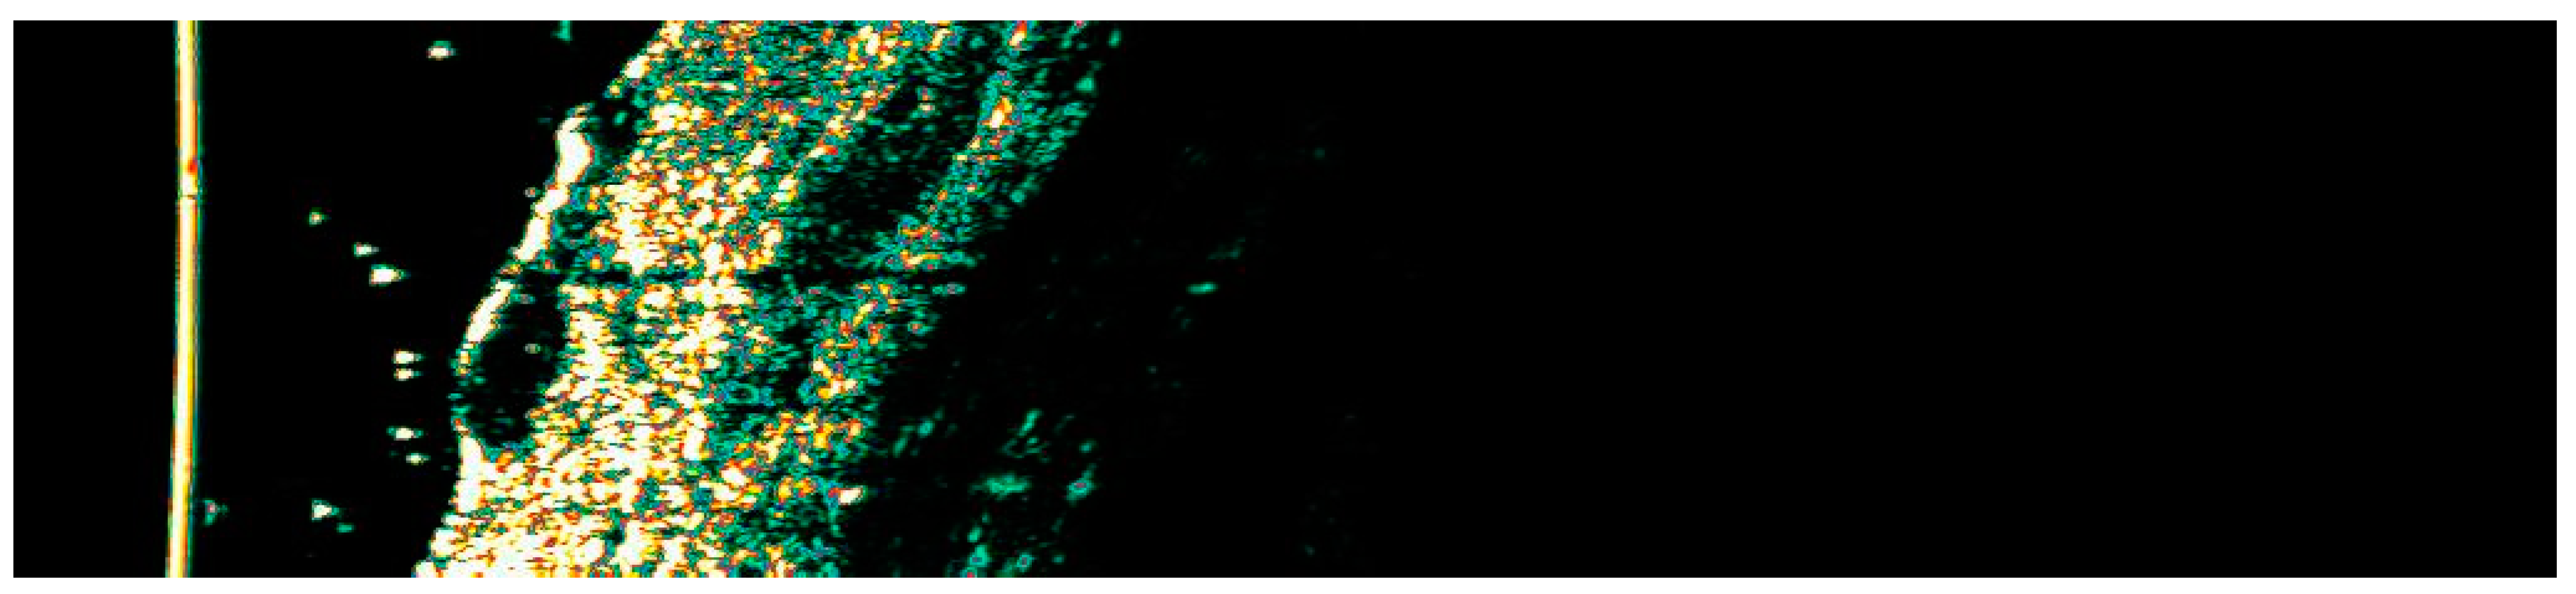

3.1. Clinical and Dermoscopic Involution of HIFU-Treated Basal Cell Carcinoma

| Number of Changes | Vascular Patterns | Pigment Structures | Non-Pigmented Structures | ||||||||||||||||

|---|---|---|---|---|---|---|---|---|---|---|---|---|---|---|---|---|---|---|---|

| Ambrozing Linear | Short Linear | Loop-like Linear | Bent Linear | Clod-like Linear | Radially Arranged | Segmentaly Arranged | Reticular | Segmentally Arranged Linear | Radially Arranged Linear | Angular Linear | Small Gray-Blue Globules | Large Gray-Blue Globules | White Lines | Small White Structureless Areas | Pink Structureless Areas | White-Yellow Globules | Orange Globule–Crust | Rosettes | |

| 1. | X | X | X | X | 2 | ||||||||||||||

| 2. | X | X | X | 2 | |||||||||||||||

| 3. | X | X | 1 | ||||||||||||||||

| 4. | X | 1 | |||||||||||||||||

| 5. | X | X | 2 | ||||||||||||||||

| 6. | X | X | 2 | ||||||||||||||||

| 7. | X | X | 1 | X | |||||||||||||||

| 8. | X | X | 2 | ||||||||||||||||

| 9. | X | X | 2 | X | |||||||||||||||

| 10. | X | X | 1 | X | |||||||||||||||

| 11. | X | X | X | X | 2 | ||||||||||||||

| 12. | X | 2 | |||||||||||||||||

| 13. | X | X | X | 2 | |||||||||||||||

| 14. | X | X | 2 | ||||||||||||||||

| 15. | X | X | X | X | X | 1 | |||||||||||||